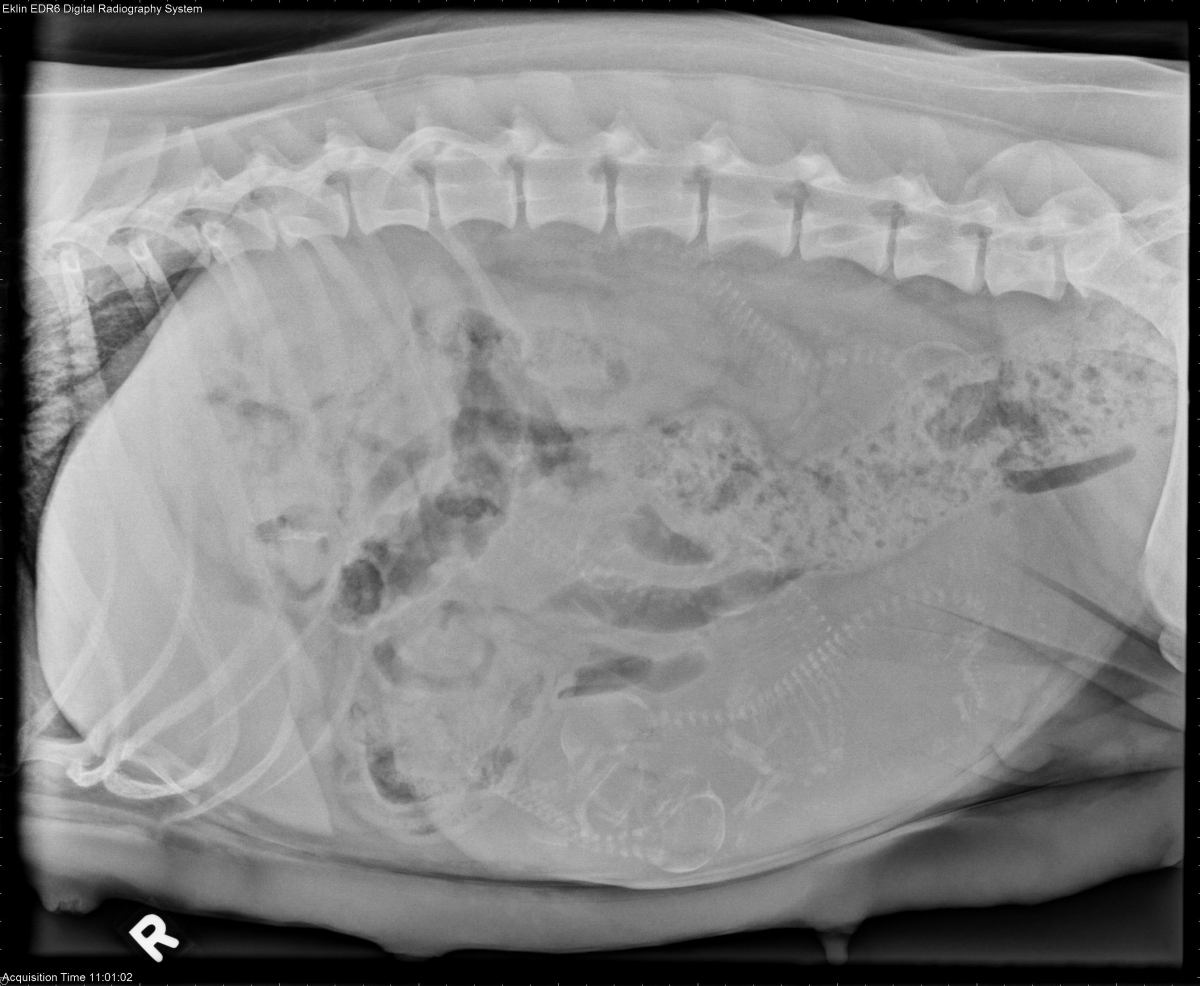

From www.veterinaryradiology.net

3 year old Bassett Hound Basset Hound Gestation This duration, however, can be. This means that they are pregnant for an average of nine weeks before they give birth to. — dogs pass through the stages of pregnancy quickly. They will have all the signs of a pregnancy without the pups. This period can be broken. Like most other breeds, basset hounds are pregnant for about 63. Basset Hound Gestation.